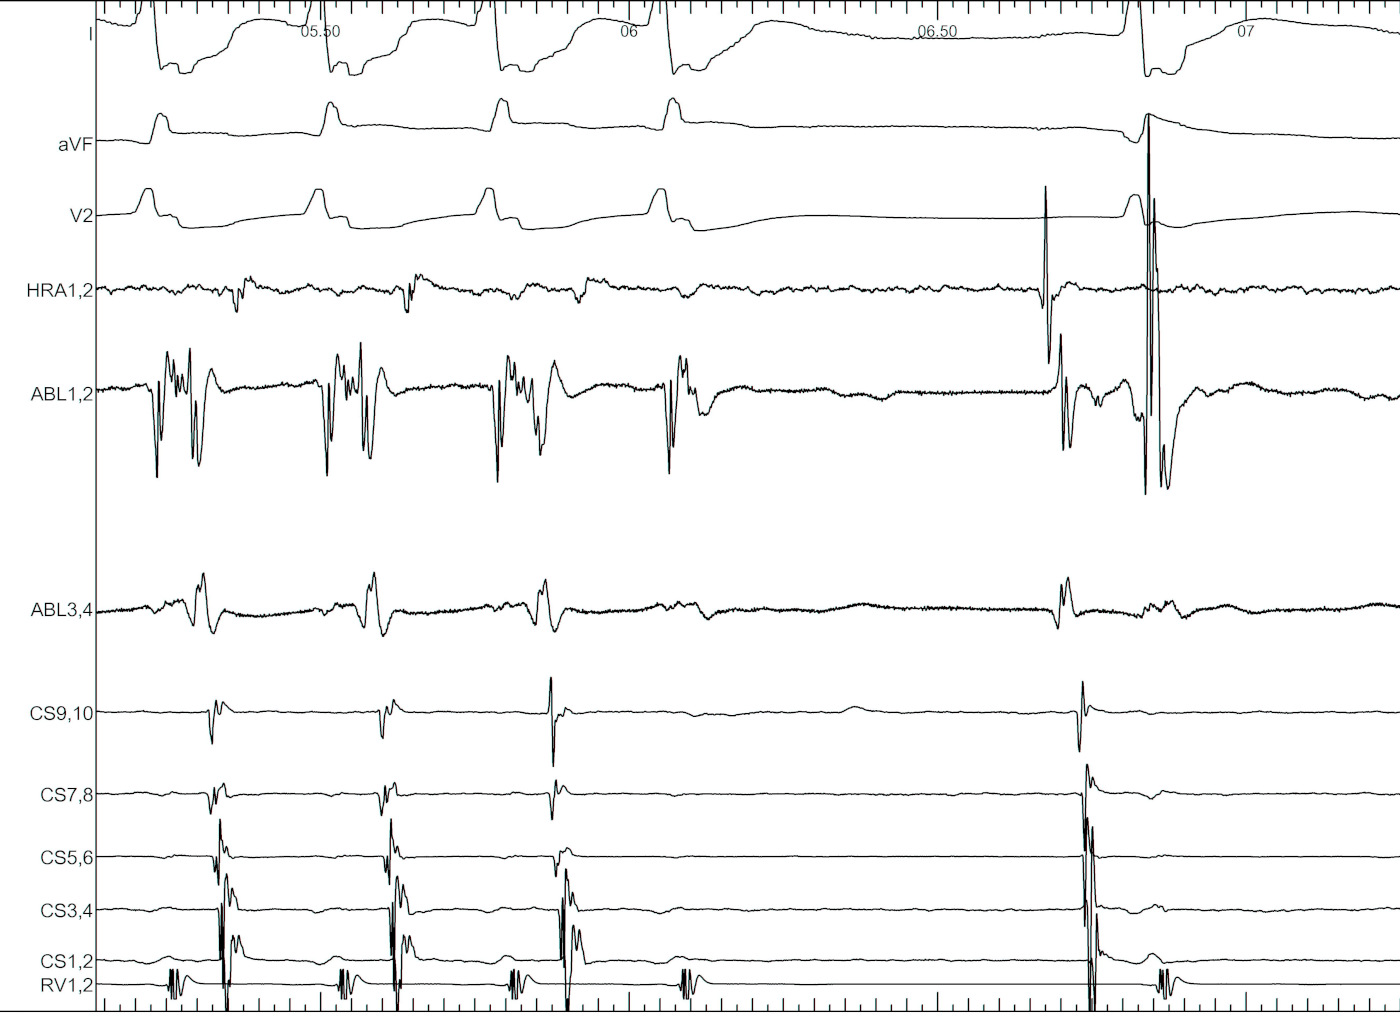

Pacing from LV

lv_catheter.png

Pacing from CS tributary

cs_pacing.jpg